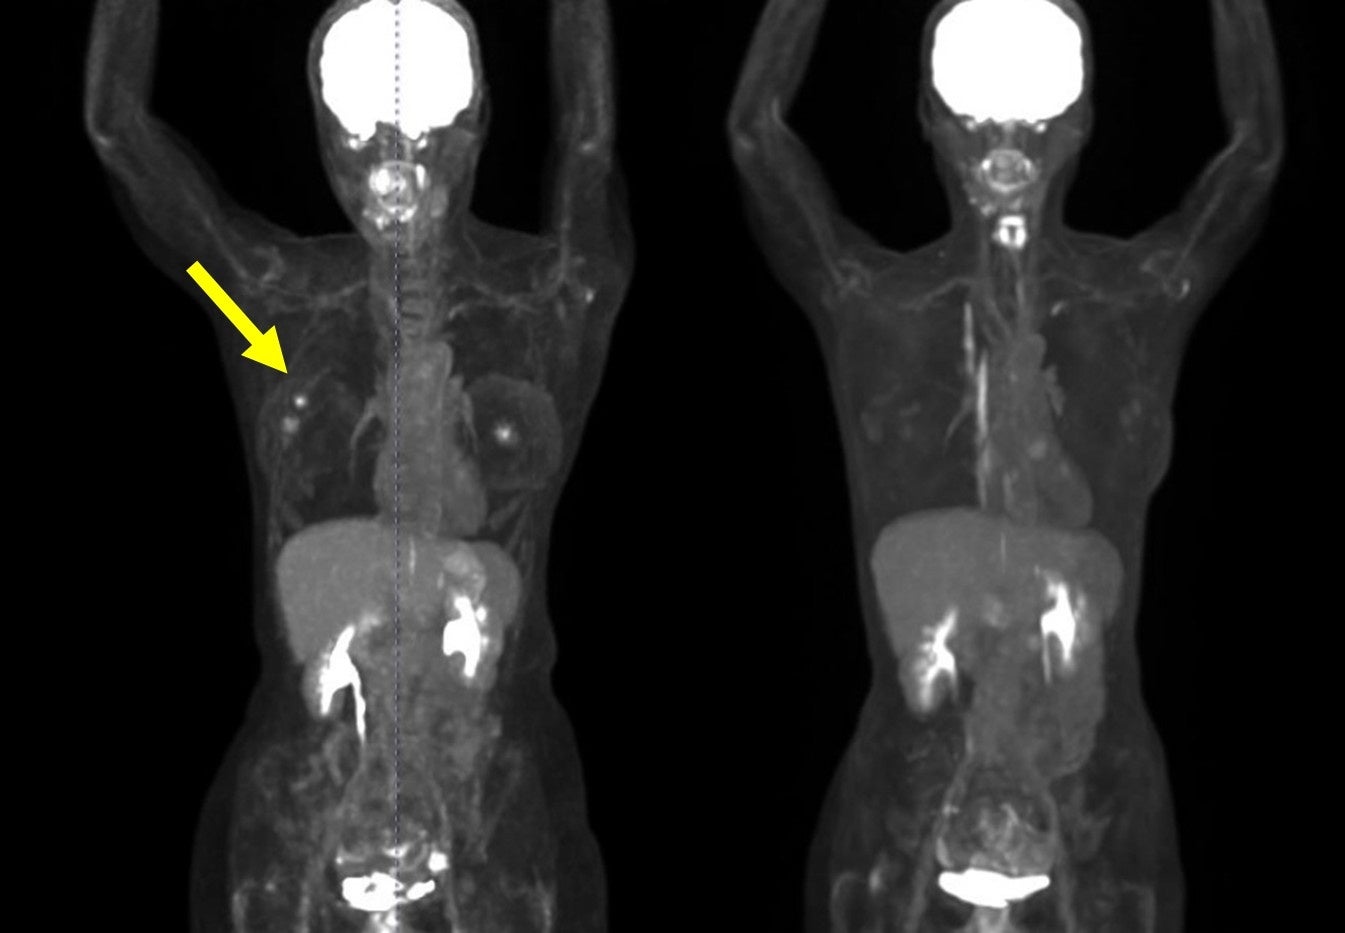

・FDG-PET陽性の浅在性腫瘍に対するBNCT(jRCTs031240204)治療10例目:初発乳がん(未手術)

FDG-PETにおける集積がSUV5からSUV1へ低下。治療1カ月後の時点で触診上腫瘍が確認できなくなり、その後2~4カ月の画像診断においても腫瘍は確認されませんでした。(効果判定はCR)